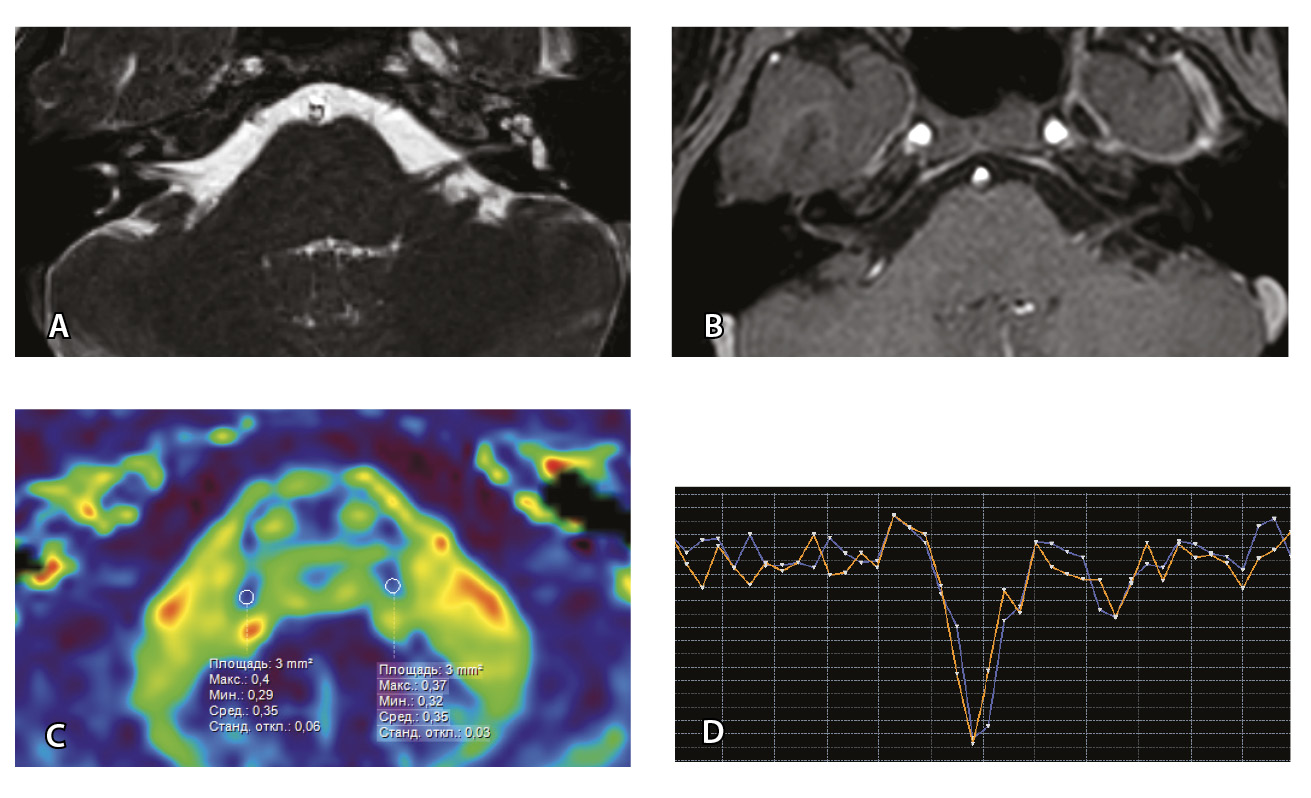

Проведена МП-МРТ головного мозга и черепно-мозговых нервов. Заключение: МР-признаки локального участка повышенного накопления контрастного вещества правым ЛН во внутреннем слуховом проходе – изменения могут соответствовать невриту ЛН (рис. 6).

Рис. 6. Пациентка З. Магнитно-резонансная томография (МРТ) головного мозга: А – прицельная T2-SSFP на область мосто-мозжечкового угла; Б – Т1-взвешенное изображение с контрастным усилением; В – диффузионно-тензорная МРТ (фракционная анизотропия, ФА); Г – Т2*-перфузия. На изображении T2-SSFP патологические изменения на уровне прохождения лицевых нервов во внутренних слуховых проходах не определяются (А). При контрастировании отмечается накопление контрастного вещества правым лицевым нервом во внутреннем слуховом проходе (Б, красная стрелка). На уровне моторных ядер лицевого нерва в заднем отделе варолиевого моста на изображениях ФА на стороне поражения отмечается минимальное уменьшение показателя ФА до 0,33 (В, черная стрелка) и признаки гипоперфузии справа (Г, оранжевый график) по сравнению с контралатеральной стороной (Г, синий график). Данный пример демонстрирует типичные изменения при мультипараметрической МРТ у пациента с параличом Белла